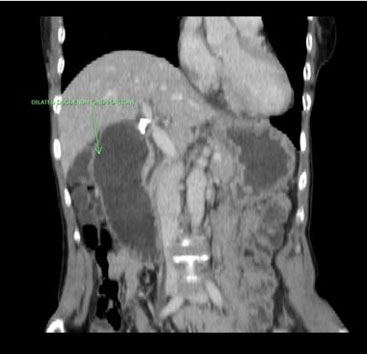

For further identification, we performed 18F-fluorodeoxyglucose position emission (FDG PET-CT), which demonstrated a high FDG uptake in the right kidney and left ilium of this patient with SUVmax values of 8.1 and 4.8, respectively (Figure 2B and Figure 2C). Additional enhanced dynamic CT of the kidney showed no tumor lesions in the right kidney. Meanwhile, the high level of FDG uptake in the right kidney was judged to be the result of urine pool due to the double renal pelvis. Given that needle biopsy did not lead to the confirmation of a histopathological diagnosis, incisional biopsy was performed. Thus, we observed that the tumor was composed of proliferating round-shaped cells with eosinophilic or clear cytoplasm. Via immunohistochemistry, we confirmed that the tumor cells were positive for PAS, but negative for HMB45, S100, and desmin. Moreover, occasional vein tumor embolisms were observed. These findings were suggestive of PEComa (perivascular epithelioid tumor) or ASPS. Additional reverse transcriptase polymerase chain reaction (RT-PCR) using a fresh frozen sample of the biopsy demonstrated the presence of ASPSCR1-TFE3 gene fusion. Therefore, the tumor was diagnosed as ASPS based on the expression of this characteristic fusion gene.

Figure 2: MRA image showing tumor hypervascularity in tumor of the left ilium (A). 18F-FDG PET-CT image demonstrating increased FDG uptakes in the right kidney (B) and left ilium (C). The SUVmax values are 8.1 (B) and 4.8 (C), respectively.

Additionally, ASPS occasionally develops bone metastasis [1],[2], and thus, possibly presents a hidden primary lesion somewhere in the deep soft tissue when the bone lesion is overt, making it difficult to identify the primary tumor in the soft tissue. For this reason, the other lesions throughout the whole body should be investigated using radiological methods if the bone lesion strongly suggests ASPS histology based on the biopsy. For this reported case, we performed 18F-FDG PET-CT, when the definite diagnosis indicated ASPS after the biopsy. The results of this examination revealed useful information that suspected lesions were present in the left ilium and right kidney. Thus, other soft tissue lesions, that is, doubtful soft tissue primary ASPS, were ruled out. We were able to exclude the possibility of the occurrence of renal tumors via additional enhanced dynamic CT. The SUVmax values corresponding to 18F-FDG PET-CT images are generally higher for high-grade sarcomas, such as undifferentiated pleomorphic sarcoma, angiosarcoma, leiomyosarcoma, and rhabdomyosarcoma, than for low-grade sarcomas [13]. However, information on the clinical application of 18F-FDG PET-CT in cases of ASPS is limited. Only three reports on soft-tissue ASPS have demonstrated high SUVmax values (5.9, 10.1, and 8.8) [14],[15],[16]. Thus, the SUVmax values corresponding to ASPSs vary widely and may not always reflect their tumor activity. Further, our findings following PET-CT of the ilium did not show any benign lesion as indicated by the findings of the other radiological examinations. The most important point to be taken into consideration is that the results demonstrated that the ilium is the primary site of ASPS.